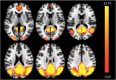

Results: A spatial pattern consistent with the default mode network (DMN) could be identified by independent component analysis. DMN activity was enhanced in APOE4 carriers and related to cortical iron burden. APOE4 and cortical iron synergistically interacted with DMN activity. Secondary analysis revealed a positive, APOE4 associated, relationship between cortical iron and DMN connectivity.